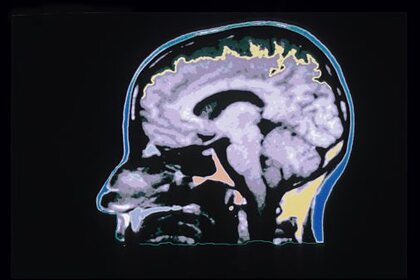

Специалисты выяснили, что есть специфичные скопления клеток вокруг кровеносных сосудов, которые определяют места, где опухоли могут быть злокачественными. По их мнению, именно эти участки могут являться рассадниками злокачественного прогрессирования, то есть процесса из-за которого опухоль быстро и неконтролируемо разрастается. Отмечается, что данное исследование имеет огромное значение, так как оно позволит с большей вероятностью определять, когда опухоль головного мозга становится злокачественной.